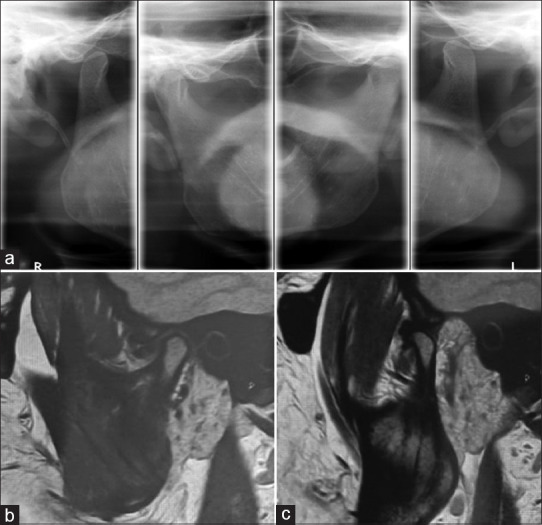

Materials and methods: Two cases diagnosed with chronic recurrent dislocation of TMJ were selected for the study. A three-dimensional virtual model was reconstructed from cone-beam computed tomography (CBCT) images of a patient. The AR visualisation was created by developing an Android app which superimposed the virtual model and the TMJ in real time. The skin puncture point was marked on the skin, and the needle was guided to the upper compartment of the joint using this superimposed view to perform TMJ arthrocentesis.

Results: Puncture with the AR method was successful in both the cases with direct access to the upper compartment of TMJ. Pain had reduced completely in both cases during 30- and 60-day follow-up periods; maximum mouth opening had reduced by an average of 4.33 mm after 60 days postoperatively, and clicking sound was completely absent after 14-day follow-up period.